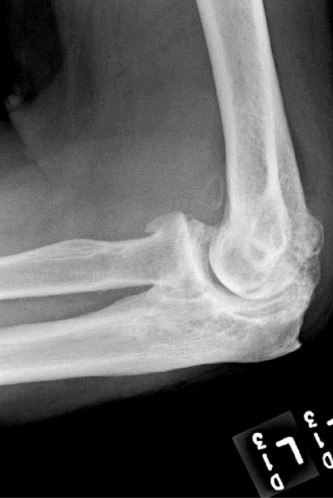

The correct answer is (E). Given that her rotator cuff has atrophied and has fatty infiltration to the point where there are equal parts fat and muscle, this is considered an irreparable rotator cuff tear. Repair should not be attempted because of poor outcomes following repair (see last two paragraphs of this discussion below). A reverse total shoulder arthroplasty is an alternative to repair that should be used in cases of massive, irreparable rotator cuff tears. It is a semi-constrained prosthesis that restores function in patients with massive rotator cuff tears by constraining a concave humeral cap inferior to a semispherical glenoid component (glenosphere). This creates an inferior force-couple and a fulcrum that replaces the stabilizing function of the infraspinatus maintaining a center of rotation around which the shoulder can move. This allows the deltoid to abduct and flex the shoulder without causing the humerus to migrate superiorly and about the acromion. In an elderly patient with a massive, irreparable rotator cuff tear (as in this patient), a reverse total shoulder arthroplasty is the procedure of choice.

It should be noted that reverse total shoulder arthroplasty is also the procedure of choice in patients with cuff-tear arthropathy (aka rotator cuff arthropathy). Characteristics of cuff-tear arthropathy include superior migration of the humerus due to a massive rotator cuff tear, glenohumeral joint destruction, subchondral osteoporosis, and humeral head collapse (see Fig. 2–17). A reverse total shoulder

arthroplasty in this case serves the purpose of eliminating pain caused by glenohumeral joint arthritis while restoring functional motion and is the procedure of choice in patients with cuff-tear arthropathy.

Figure 2–17_X-rays of a patient showing evidence of cuff tear arthropathy. The humerus is migrated superiorly, the glenohumeral joint is destroyed, there is subchondral osteoporosis, and the humeral head is collapsed. (From Ecklund KJ, Lee TQ, Tibone J, Gupta R. Rotator cuff tear arthropathy. _J Am Acad Orthop Surg. 2007;15(6):340–349.)

A hemiarthroplasty (Answer A) was previously the procedure of choice for cuff-tear arthropathy until the reverse total shoulder prosthesis was developed. A hemiarthroplasty reliably relieves pain, but it does not restore function as well as the reverse total shoulder. Also, if the patient had a previous coracoacromial ligament release or anterior deltoid detachment, they are at risk for anterosuperior escape of the humeral head after hemiarthroplasty.

A total shoulder arthroplasty (Answer B) is contraindicated in the case of cuff-tear arthropathy because of glenoid component loosening. If a glenoid component is used in this patient, the superior translation of the humeral head component on the glenoid component could cause it to loosen and rock, producing a “rocking-horse” glenoid component.